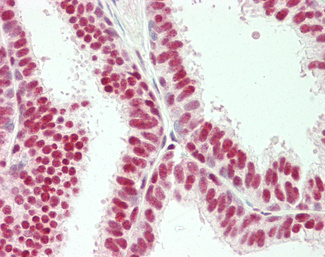

Estrogen Receptor / ESR1

Anti-ER Alpha / Estrogen Receptor antibody IHC staining of human breast. Immunohistochemistry of formalin-fixed, paraffin-embedded tissue after heat-induced antigen retrieval. Antibody LS-B10527 dilution 1:100.